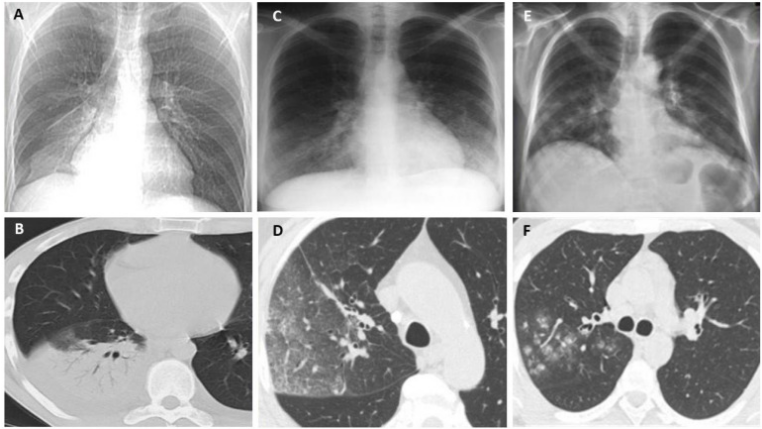

Lemierre综合征(LS)是以法国医生Andre Lemierre的名字命名,他在1936年报告了20例由口咽感染引起的厌氧败血症。(1)流行病学:在抗生素广泛应用的年代,LS的发病率急剧下降。自70年代后期口腔感染中经验性抗生素的使用减少,报告的病例数量稳步上升,被称为“被遗忘又重现的疾病”,发病率为每年1/10000000,通常为青少年和年轻人,即使使用适当的抗生素和治疗,报道死亡率也在5%~18%之间。(2)致病菌:导致LS的致病菌通常为坏死梭杆菌(>70%),它是严格的专性厌氧革兰氏阴性杆菌。(3)病理生理:首先由于细菌、病毒致咽部黏膜损伤,在此基础上出现坏死梭杆菌的二重感染:①感染至咽外侧间隙和颈部软组织,引起外源性压迫,出现炎症、水肿;②内源性闭塞,出现血管内凝血。在上述基础上发生颈内静脉脓毒性血栓形成;感染性栓子从任何一条静脉播散,都可能导致肺、胸膜、关节、骨骼、肌肉、肝、脾、肾等多处器官受累。(4)临床特征:①口咽感染;②颈内静脉血栓性静脉炎感染延伸至颈部旁间隙;③脓毒性栓子播散引起菌血症、脓毒性休克。(5)诊断:①血培养:培养时间需要6~8天,阳性率低;②分子生物学方法:快速且准确,有助于早期诊断;③BALF、m-ROSE、NGS等。LS的Sinave诊断标准:①口咽部的原发感染;②脓毒败血症;③颈内静脉感染性栓塞;④远处脏器转移性化脓灶。(6)治疗:①抗菌药物治疗:碳青霉烯类、β-内酰胺/β-内酰胺酶抑制剂联合甲硝唑是治疗LS最有效的药物。②抗凝治疗。③外科治疗。(1)定义:齿垢密螺旋体是一种螺旋形的革兰氏阴性厌氧菌,属解糖密螺旋体,与口腔以及牙周感染性疾病密切相关。(2)流行病学:关于齿垢密螺旋体,近4年来仅有寥寥数篇报道,极为罕见。(3)易患人群:长期卧床、生活无法自理导致口腔卫生较差、牙周状况不理想、免疫功能低下的老年人。(4)临床症状:多为非特异性症状,可有吸入性肺炎的一系列临床表现,如咳嗽、咳痰、甚至咯血,也可有畏寒、发热等。(6)治疗:目前仍按照密螺旋体属中常见人致病螺旋体进行治疗,首选为青霉素,其他如半合成青霉素、四环素类等药物亦有较好效果。患者男性,72岁。主诉:间断咳痰、咯血1月半余,发现肺结节1月余。患者2023年2月中旬无明显诱因出现间断咳痰,咳白黄痰,痰中带血,每天5~6次,无发热,无胸痛等不适,后出现咯鲜血,咯绿豆大小血块,4~5次/天,就诊于当地医院,胸部CT提示左肺上叶占位,予莫西沙星抗感染治疗约1周后症状好转,后就诊于我院。入科后,予患者支气管镜下肺泡灌洗并将BALF送检mNGS,结果回报检出齿垢密螺旋体(序列数36条)。予哌拉西林他唑巴坦4.5 g q8h+米诺环素100 mg q12h抗感染,调整治疗方案为美罗培南1 g q8h,后期仅采用替加环素50 mg q12h治疗。抗感染治疗后,患者左肺上叶结节明显缩小。非典型病原体是一种细胞内或细胞旁的细菌病原体,无法通过革兰氏染色和传统培养基进行识别,对β-内酰胺具有内在耐药性。2022年Microorganisms杂志发表的综述显示,在CAP病因中,非典型病原体占15%,这其中,肺炎支原体位居首位,其次是肺炎衣原体,然后是嗜肺军团菌以及鹦鹉热衣原体等。1976年夏天宾夕法尼亚州费城Bellevue-Stratford酒店举行的为期3天的美国退伍军人协会年度大会上,嗜肺军团菌感染首次被发现。(1)流行病学:既往军团菌肺炎的病死率可达10%~15%,院内感染死亡率可达25%~50%。随着喹诺酮类药物的临床应用,该病病死率有所下降。该病发病具有季节性,全年均可发生,以6~10月发病最多。(2)致病菌:军团菌肺炎的致病菌通常为嗜肺军团菌血清型1,约占90%,是一种需氧革兰氏阴性杆菌,细胞内寄生菌,双相生存周期。(3)传播途径:军团菌广泛存在于自然界中,尤其是温暖潮湿的环境,如人工冷水、天然水源、潮湿土壤等。军团菌感染多通过吸入受污染的人造水源(如淋浴、管道、空调系统等)产生的含军团菌气溶胶。(4)易患人群:>50岁、吸烟、免疫抑制(尤其是细胞免疫抑制)、合并慢性心肺疾病等。(5)影像学表现:肺部变化通常为单侧,主要局限于下叶,但也可能出现在两侧,包括肺部的上下部分;肺部的炎症变化可表现为3种类型的浸润——肺泡型、间质型和局灶型。军团菌肺炎的胸部X线片和CT最具特征的表现是不规则形状的肺组织大面积固结,靠近肋和/或水平胸膜,有空气支气管造影征象和局灶性肺泡-间质磨玻璃样混浊。

图源:J Clin Med, 2022, 11(20):6126.

(6)临床表现:男性多见,约90%的患者体温超过38.5°C;呼吸道症状主要有咳嗽、咳痰、气促;神经肌肉系统表现为头痛、肌痛、关节痛;会出现相对缓脉,多脏器损害。(7)实验室指标:低钠血症,低磷血症,磷酸激酶、肝酶、ESR、CRP水平升高等。(8)影像学检查:军团菌肺炎的影像学表现具有多样性,其较为特征的改变是磨玻璃影间混杂边界分明的实变区。(9)病原学检测:分离培养(BALF培养阳性率最高)以及抗原抗体检测等(表1)。(10)治疗:①抗感染治疗:主要为经验性治疗,首选氟喹诺酮类抗生素。②尚未明确的治疗方式:药物联合治疗,如喹诺酮类+大环内酯类,以及糖皮质激素治疗,目前尚无指南共识推荐。③对于重症军团菌肺炎,可以联合ECMO(可以提高重症患者生存率)。患者,男,34岁,军人。主因“诊断慢性粒细胞白血病13年余,咳嗽6天,发热2天”于2022年7月16日收入血液科,后因喘憋加重于2022年9月1日转入我科。患者于2021年诊断亚临床甲减、桥本病,未治疗。既往有多次输血史。个人史及家族史无特殊。2008年诊断慢性粒细胞白血病,口服伊马替尼治疗约1年,后未规律监测。2020年4月自行口服伊马替尼治疗至2022年7月。2022年7月初在外出差期间发现身上多发出血点,2022年7月9日查血常规提示白细胞升高、血小板降低,具体报告未见,自行口服达沙替尼治疗,后出现腹泻,自行停药。2022年7月11日出现咳嗽,进行性加重,夜间无法入睡,伴少量黄色黏痰。2022年7月14日因头晕、乏力、腹泻加重,就诊于我院急诊,体温38.7°C,完善血常规、生化、凝血、感染指标、胸部CT,考虑为慢性粒细胞白血病加速期、肺部感染、电解质紊乱、凝血功能异常。2022年7月16日收入我院血液科。入院后相关检查显示:BALF细胞分类中性粒细胞占18%,细胞总数0.36×106。BALF GM试验1.146 μg/L。BALF及肺组织mNGS均回报嗜肺军团菌。经过抗感染治疗,患者病情好转。鹦鹉热是一种人畜共患传染病。鹦鹉热衣原体是一种专性真核细胞寄生、具有独特的发育周期、革兰氏阴性的病原菌。(1)流行病学:一年四季均可发病,秋冬季发病率升高。(2)易患人群:主要发生于中老年人群,男性多于女性,50%以上有鸟类或家禽接触史。(4)诊断:①影像学检查(胸部X线片、胸部CT)最常见的表现为肺叶变化,常合并支气管充气征等。②动脉血气分析。③BALF NGS可以明确诊断。(5)治疗:首选治疗方案为四环素类药物,包括盐酸四环素、多西环素、米诺环素。妊娠期或儿童患者可以使用大环内酯类抗生素治疗,如阿奇霉素和红霉素,疗程为7天。患者女,51岁。主诉:发热6天,咳嗽、憋喘4天,于2019年11月27日入院。既往体健,近3个月经量增多,当地诊断子宫肌瘤、黏膜下肌瘤,宫颈病变。入我院1周前发现贫血予输血。体检示右肾囊肿。家族史:父母已故。家中养3只鸡。患者于2019年11月21日无明显诱因出现发热,多于午后出现,波动在38.3°左右,就诊于当地医院。次日完善胸片示肺部感染,予哌拉西林他唑巴坦、氨曲南抗感染治疗(具体不详)。2019年11月23日出现憋喘、咳嗽,活动后憋喘明显加重,咳嗽为刺激性干咳,无咳痰。上述症状影响患者的工作及生活。患者因憋喘进行性加重于2019年11月26日转入我院急诊科,胸部CT:双肺感染性病变,右肺为著;双侧胸腔积液。急诊给予头孢哌酮舒巴坦3 g bid静滴等治疗。为进一步检查及治疗,以“肺部感染"收入我科。入院后予行气管镜检查,BALF和血NGS均检出鹦鹉热衣原体序列【对于无法耐受气管镜检查的重症患者,血NGS也是重要的诊断参考】。经过积极的抗感染治疗,患者病情得到缓解,肺部病变吸收明显。惠普尔养障体是一种杆状的革兰氏阳性细菌,可以引起全身性感染性疾病。肠道是惠普尔养障体唯一已知的天然生态位。目前该细菌已经广泛发现在各种样本中,包括BALF、唾液、尿液、血液、粪便、淋巴结等。惠普尔养障体可以从口腔菌群中吸入,导致社区获得性和吸入性肺炎,严重者可能发生呼吸衰竭甚至死亡。(1)流行病学:惠普尔养障体感染所致疾病常见于高加索人种,在亚洲和非洲人群中非常罕见。其发病率约为百万分之一。(2)易感人群:HIV阳性患者、下水道工人、流浪汉等。易感人群细菌携带率以及载量显著高于普通人。近年来由于对惠普尔养障体肺炎认识程度的提高以及诊断技术的改进,病例报告的数量也在不断增加。因此该病的实际发生率高于预期。(3)宿主:普遍认为惠普尔养障体没有重要的非人类宿主。(4)临床表现:惠普尔养障体感染所致肺炎具有广泛的非特异性临床表现。疾病早期的患者可能会出现感染、发热、关节炎和关节痛的症状;疾病中期出现腹泻、吸收不良和体重减轻等综合症状;疾病晚期则可能累及各个生理系统,在80%~90%的病例中,第一个前驱体征是关节炎和/或关节痛。入院患者则多以呼吸急促和咳嗽为主诉。(5)实验室检查及影像学:贫血、低白蛋白血症及ESR或CRP水平升高,胸部CT可能出现多种改变,包括磨玻璃影、肺结节、胸膜增厚和渗出性病变依据与肺脓肿非常相似的气液平等。(6)诊断方法:常规实验室检查常出现非特异性结果,既往最常见的诊断方法是组织病理学和PCR。近年来BALF mNGS已被证明能够提供更全面的气道细菌感染情况,识别并筛查诱发肺炎的惠普尔养障体。(7)治疗:目前推荐的治疗方案包括:头孢曲松(2 g qd) 或美罗培南(1 g tid),持续14天,后续口服复方磺胺甲噁唑(TMP-SMZ)2个月。若治疗过程中患者表现出对TMP-SMZ不耐受,则可使用多西环素。肺孢子菌肺炎是由卡氏肺孢子菌引起的呼吸系统感染,是一种发生于免疫功能受损个体中的感染,可能会危及患者生命。(1)流行病学:2012—2022年肺孢子菌肺炎发病率从2.2/10万增加至3.9/10万,30天死亡率为18.2%。(2)易感人群:HIV阳性患者,血液病,实体器官移植患者。(3)临床表现:具有非特异性。患者有进行性呼吸困难、低热等表现。(4)影像学表现:双侧弥漫性间质浸润;伴有弥漫性斑片状实变和磨玻璃影。(5)诊断:①乳酸脱氢酶(LDH)水平增加常作为HIV感染者中疑诊肺孢子菌肺炎的临床标志。②1,3-β-D-葡聚糖水平升高时,也应怀疑肺孢子菌肺炎。③DFA、qPCR检测。(6)治疗:①首选TMP-SMX治疗,剂量为15~20 mg/(kg·d),分3次或4次给药。治疗持续时间一般为21天。目前临床也有采取TMP-SMX联合卡泊芬净治疗。②辅助治疗:动脉血气显示PaO2<70 mmHg或低氧血症,建议给予糖皮质激素辅助治疗。患者男,80岁。主诉:呼吸困难4天,发热1天。于2021年2月5日入呼吸科。2020年11月发现重症肌无力(TA型),在我院神经内科住院,接受溴吡斯的明和甲泼尼龙治疗(最大剂量11片/天,规律减至4片/天)。入院后相关检查:WBC 7.31×109/L,CRP 14.2 mg/L,IL-6 394.3 pg/ml。BALF分类计数:巨噬细胞56%,中性粒细胞32%,淋巴细胞12%,嗜酸性粒细胞0。G试验355 pg/ml。床旁ROSE发现肺孢子菌包囊,NGS测序结果亦提示耶氏肺孢子菌。毛霉病是由广泛存在于自然界中的毛霉目菌属导致的感染,感染肺部多为急进性感染,可蔓延至相邻结构或血行播散至其他器官。(1)流行病学:全球发病率为1.2/10万,印度发病率为14/10万,是全球发病率的14倍。全球死亡率为57%。(2)易感人群:主要为免疫抑制患者,如流感、新冠病毒感染、糖尿病、器官移植患者等。(3)临床症状:具有非特异性。常伴有典型的肺炎表现伴咯血。(4)影像学表现:①局灶性实变、肿块、胸腔积液、多发性结节;②晕轮征提示血管侵入性真菌感染;③反晕征在毛霉菌患者中较其他侵袭性霉菌感染更常见。④伴或不伴空气新月征的空洞病灶在新冠病毒感染后毛霉病中更常见。(5)诊断:为尽快确诊,应在适当的临床情况中早期考虑毛霉病,并积极完善侵入性检查,通过组织病理学识别出具有毛霉目典型结构的微生物可能是感染的唯一证据。PCR检测可能有助于识别致病菌种。(1)流行病学:2022年年中,34个国家报告了28.8万例马尔尼菲篮状菌病例,东南亚及中国南方地区(广东、广西、福建、云南)多见。马尔尼菲篮状菌为双相型真菌,在25°C时为霉菌形态,在37°C时为酵母菌形态。(3)传播途径:尚不明确,空气传播、直接接种可产生。(4)易感人群:HIV阳性患者(89.9%),以及其他免疫受损患者(10.1%)。(5)临床表现:约70%的马尔尼菲篮状菌感染患者会出现皮肤损伤,面部、胸部、四肢随丘疹中心坏死,呈现脐状丘疹外观。(6)影像学表现:具有非特异性。可有磨玻璃改变、间质性浸润、肺大疱、空洞。(7)治疗:①诱导治疗:中重度患者(多器官受累),可选用两性霉素B治疗2周;轻度患者(仅有皮肤损伤),可选用伊曲康唑治疗。②巩固治疗:对于任意患者,建议选用伊曲康唑进行10周巩固治疗。③维持治疗:对于免疫受损患者,建议继续维持治疗,伏立康唑可作为替代用药。诺卡菌是一类有菌丝、无动力的需氧革兰氏阳性菌,在人类中可造成局部或全身性疾病,广泛存在于土壤、空气、污水和腐生物中。(1)传播途径:多通过吸入受污染的粉尘感染,可传播至呼吸道或消化道,形成局部或经血行播散至脑、肝、肾等部位。(2)易感人群:免疫功能受损患者(HIV感染、器官移植后慢性基础性肺病等)。(4)影像学特征:多见单侧/双侧肺结节,也可见肺实变、肿块、胸腔积液、网状结节。(5)诊断:根据患者的临床表现(易感因素、临床症状、CT表现)以及检查检验结果(M-ROSE、组织病理学、微生物学)进行判断。(6)治疗:抗诺卡菌治疗,重建免疫功能,降低病死率。首选TMP-SMX,15 mg/(kg·d),静脉注射。备选方案:亚胺培南西司他丁500 mg静脉注射q6h+阿米卡星7.5 mg静脉注射q12h,3~4周,改为TMP-SMX口服。推荐疗程为3个月,长期使用免疫抑制者疗程为6个月。属于机会性病原体,见于免疫功能低下、免疫缺陷患者以及婴幼儿,引发肺弓形虫病。(1)流行病学:全球输血患者患病率可达33%,接受干细胞移植患者死亡率可达43.5%。(2)致病菌:刚地弓形虫,分为强毒株RH株、弱毒株Beverley株。(3)传播途径:人畜共患。摄入生肉或熟肉中的囊肿;受感染猫科动物粪便污染基质中的卵囊;速殖子的先天性传播;输血传播。(4)临床特征:免疫功能低下患者症状明显;非特异性呼吸道症状,如发热、呕吐、腹泻、皮疹等;肺外器官受累,包括肝脾肿大、颌下及颈后淋巴结肿大等。(5)诊断:①病原学检查(确诊)。涂片染色,如姬氏染色,阳性率低,易漏检;动物接种分离法,培养7天,阴性传代3次以上。②血清学实验(辅助诊断),包括染色试验、间接血凝试验、间接免疫荧光抗体试验、PCR及DNA探针。(6)治疗:在弓形虫增殖阶段,使用TMP-SMZ,联合乙胺嘧啶可增加疗效。孕妇感染首选螺旋霉素,佐用免疫增强剂。炭疽杆菌属于厌氧、革兰氏阳性、形成孢子、非运动的、杆状芽孢杆菌,外界环境抵抗力强,导致人畜共患疾病。(1)流行病学:吸入型炭疽病死亡率为85%,摄入型炭疽病死亡率为74%。皮肤型炭疽病死亡率为46%,注射型炭疽病死亡率为33%。(2)致病菌:炭疽杆菌,分为生物活性的植物形态和生物惰性的孢子形态。(3)传播途径:人畜共患。接触濒死或已死亡动物(屠宰动物);接触受污染的动物产品(皮革、骨粉肥料);食用受污染的肉类;自注射(注射受污染的毒品);院内传播。(4)临床表现:①吸入性炭疽:潜伏期1~7天;初始阶段轻度发热、疲劳、排痰性咳嗽和胸痛或腹痛。严重阶段则为高热,毒血症、呼吸困难和发绀,甚至休克、死亡。纵隔增宽是吸入性炭疽的典型表现。②胃肠道炭疽:潜伏期3~7天,病变可见于胃肠道的任何一点,发热、咽痛、吞咽困难、恶心、呕吐、厌食、腹泻等。可从血液、腹水和病变组织中分离出炭疽杆菌来明确诊断。③皮肤炭疽:潜伏期2~7天;最初可为瘙痒性皮疹,可逐渐进展为红斑和水肿包围的水疱,最后有焦痂形成。④注射性炭疽:是炭疽病的一种新型临床形式,软组织在注射部位被感染并导致毒血症和败血症。(5)诊断:炭疽病的诊断组结合患者的基本情况和临床检查检验综合判断。基本情况包括患者的病史、症状、体征、旅居史、动物接触史等。临床检验检查包括血培养(金标准)、PCR、影像学(纵隔增宽、胸腔积液和实质浸润等)、BALF或活检标本等。